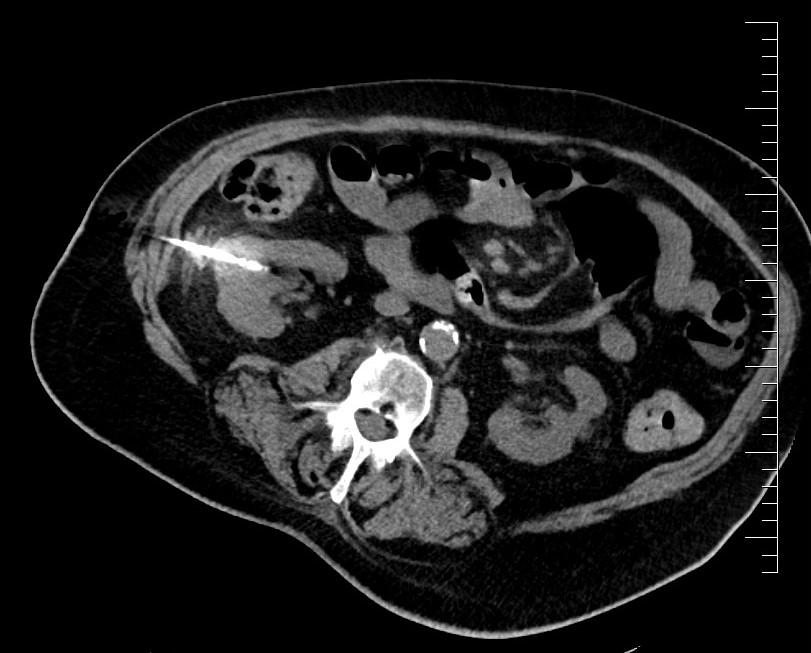

Souhrn: Cíl: Mikrovlnná ablace představuje v léčbě cT1 renálních karcinomů alternativu k resekčním výkonům. Cílem naší studie bylo retrospektivně zhodnotit onkologické výsledky a pooperační komplikace této metody. Soubor pacientů: Retrospektivní unicentrická studie obsahuje 63 pacientů, kteří podstoupili celkem 78 mikrovlnných ablací na našem pracovišti mezi lety 2012 a 2023. Výsledky: Studie prokázala výraznou vazbu onkologických výsledků na velikost tumoru. U pacientů s tumorem < 3 cm zůstalo po dobu sledování bez recidivy 86 % pacientů, v případě tumorů > 3 cm nemělo recidivu 68 % pacientů. Pooperační komplikace se vyskytly u 18 % pacientů, přičemž u 6 % pacientů se jednalo o komplikace závažné (stupeň ≥ 3 dle Clavien-Dinda). Závěr: Mikrovlnná ablace v léčbě lokalizovaných nádorů ledvin (cT1) představuje moderní a bezpečnou miniinvazivní techniku. Terapeutický výsledek je výrazně závislý na velikosti tumoru. U tumorů do 3 cm dosahuje metoda srovnatelných onkologických výsledků s podobnou frekvencí výskytu pooperačních komplikací jako resekční výkony.

Renální karcinom (RCC – renal cell carcinoma) je v České republice časté onkologické onemocnění dosahující incidence 3 100 případů za rok. Onemocnění je diagnostikováno nejčastěji mezi 65. a 74. rokem věku, přičemž u mužů je 1,7× častější. Ročně na RCC umírá přibližně 650 mužů a 390 žen [1]. Diagnostika RCC se zakládá především na zobrazovacích metodách (sonografie, CT vyšetření, výjimečně magnetická rezonance). Vzhledem k často asymptomatickému průběhu onemocnění v počátečních stadiích se často jedná o incidentalomy. V případě lokalizovaných tumorů ve stadiu cT1, tedy tumorů do 7 cm v největším rozměru, které jsou předmětem naší studie, je upřednostňovanou metodou léčby resekční výkon [2]. Optimální volbou je resekce ložiska, popřípadě nefrektomie u případů, u kterých uložení tumorózního ložiska resekci neumožňuje. Nicméně u polymorbidních pacientů, pro něž by byla celková anestezie vysoce riziková, či u pacientů se sníženou funkcí ledvin, u nichž by radikální výkon mohl vést k významné renální insuficienci, existují alternativy v podobě aktivního sledování, pozorného vyčkávání či miniinvazivních ablačních metod. Tyto varianty mohou zvolit i pacienti, kteří si velký chirurgický zákrok nepřejí [3–5]. Ablační metody lze na základě mechanizmu destrukce nádorové tkáně rozdělit na radiofrekvenční ablaci (RFA), kryoablaci a mikrovlnnou ablaci (MWA – microwave ablation).

Výkon byl prováděn mikrovlnným systémem Solero Microwave Tissue Ablation System (AngioDynamics, Inc., USA). Během ablačních výkonů byla používána frekvence 2,45 GHz a výkon v rozsahu 100–140 W. Jako aplikátor byla používána nerezová ocelová jehla s keramickým hrotem o průměru 15 G a délce 14, 19 nebo 29 cm. Jedna ablační sekvence po zavedení jehly do tumoru trvá 4–6 min podle velikosti nádoru, v průběhu jednoho výkonu jsou standardně prováděny 1–2 ablační sekvence. Maximální velikost ablační zóny udávaná výrobcem je 54 × 39 mm na jednu sekvenci. Po skončení ablace tumoru se během vytahování jehly provádí ablace-koagulace punkčního kanálu (track ablace). Výkon je prováděn v analgosedaci za přítomnosti anesteziologa, pacienti snášejí výkon dobře. Celková doba výkonu vč. polohování pacienta a přípravy CT pracoviště je 60–90 min (obr. 1).

Pacienti byli po provedené MWA pravidelně sledováni pomocí CT vyšetření (kontrastní CT vyšetření hrudníku, břicha a malé pánve), první CT po výkonu bylo provedeno v rozmezí 3–6 měsíců. Dále byli pacienti sledováni s ročním intervalem, přičemž část pacientů byla sledována cestou spádových urologických ambulancí, v nichž byla četnost i celková doba sledování variabilní. Pro rozlišení časných recidiv a nekompletní MWA bylo za recidivu považováno jakékoliv nově zjištěné viabilní ložisko na kontrolním CT vyšetření následujícím po prvním kontrolním CT vyšetření provedeném těsně po MWA (3–6 měsíců po výkonu). Všechna lokálně umístěná viabilní ložiska zjištěná na prvním CT vyšetření 3–6 měsíců po zákroku naopak považujeme za nekompletní MWA. Případy, u kterých bylo MWA nutné 1× nebo 2× opakovat pro nekompletnost, byly pro potřeby hodnocení onkologických výsledků chápány jako jeden případ, ve výsledcích zároveň uvádíme celkový počet takto opakovaných výkonů. Doba do recidivy a doba sledování byla u těchto případů stanovena od poslední provedené MWA.